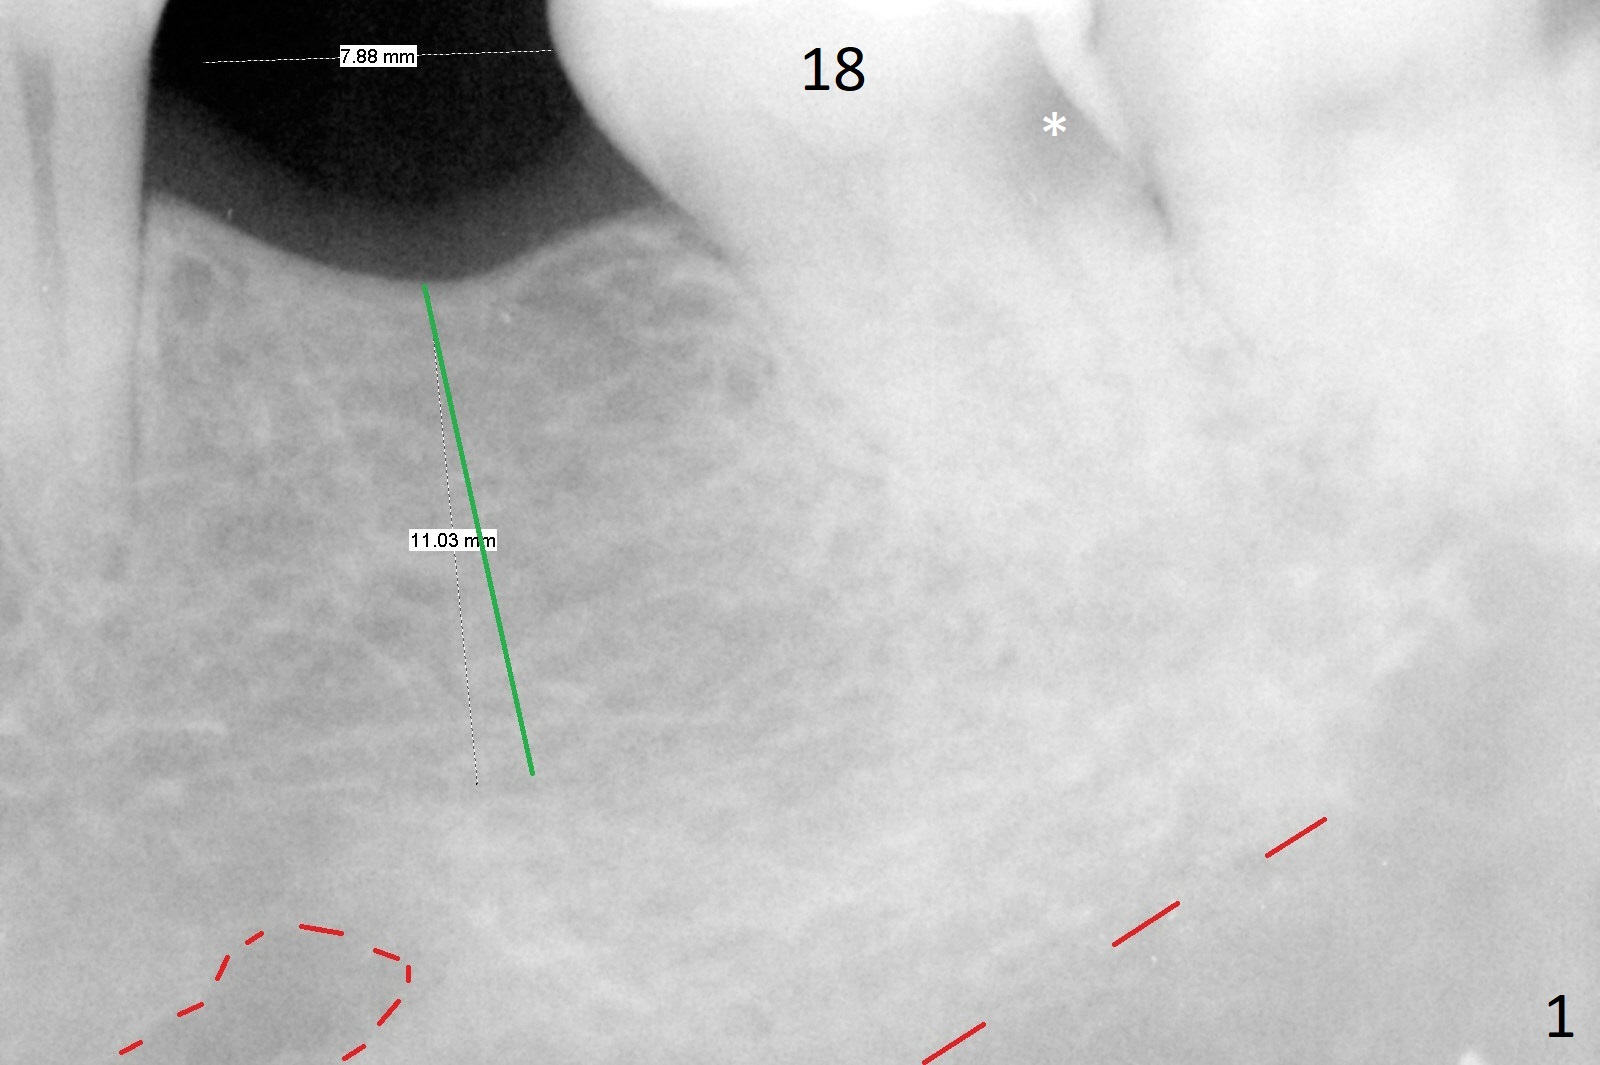

56岁女右上6植牙4年,牙冠松动两次,基台断裂一次,一直不肯做左下6植牙(图一,二,四),对合牙长长(图三:箭头;图五),因为害怕神经(图一:红虚线)损伤,导板已经介绍。IBS No Caries Xin Wei, DDS, PhD, MS 1st edition 11/20/2020, last revision 11/22/2020